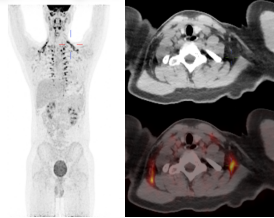

患者A未进行保暖PET/CT图像

患者A进行保暖后复查PET/CT图像